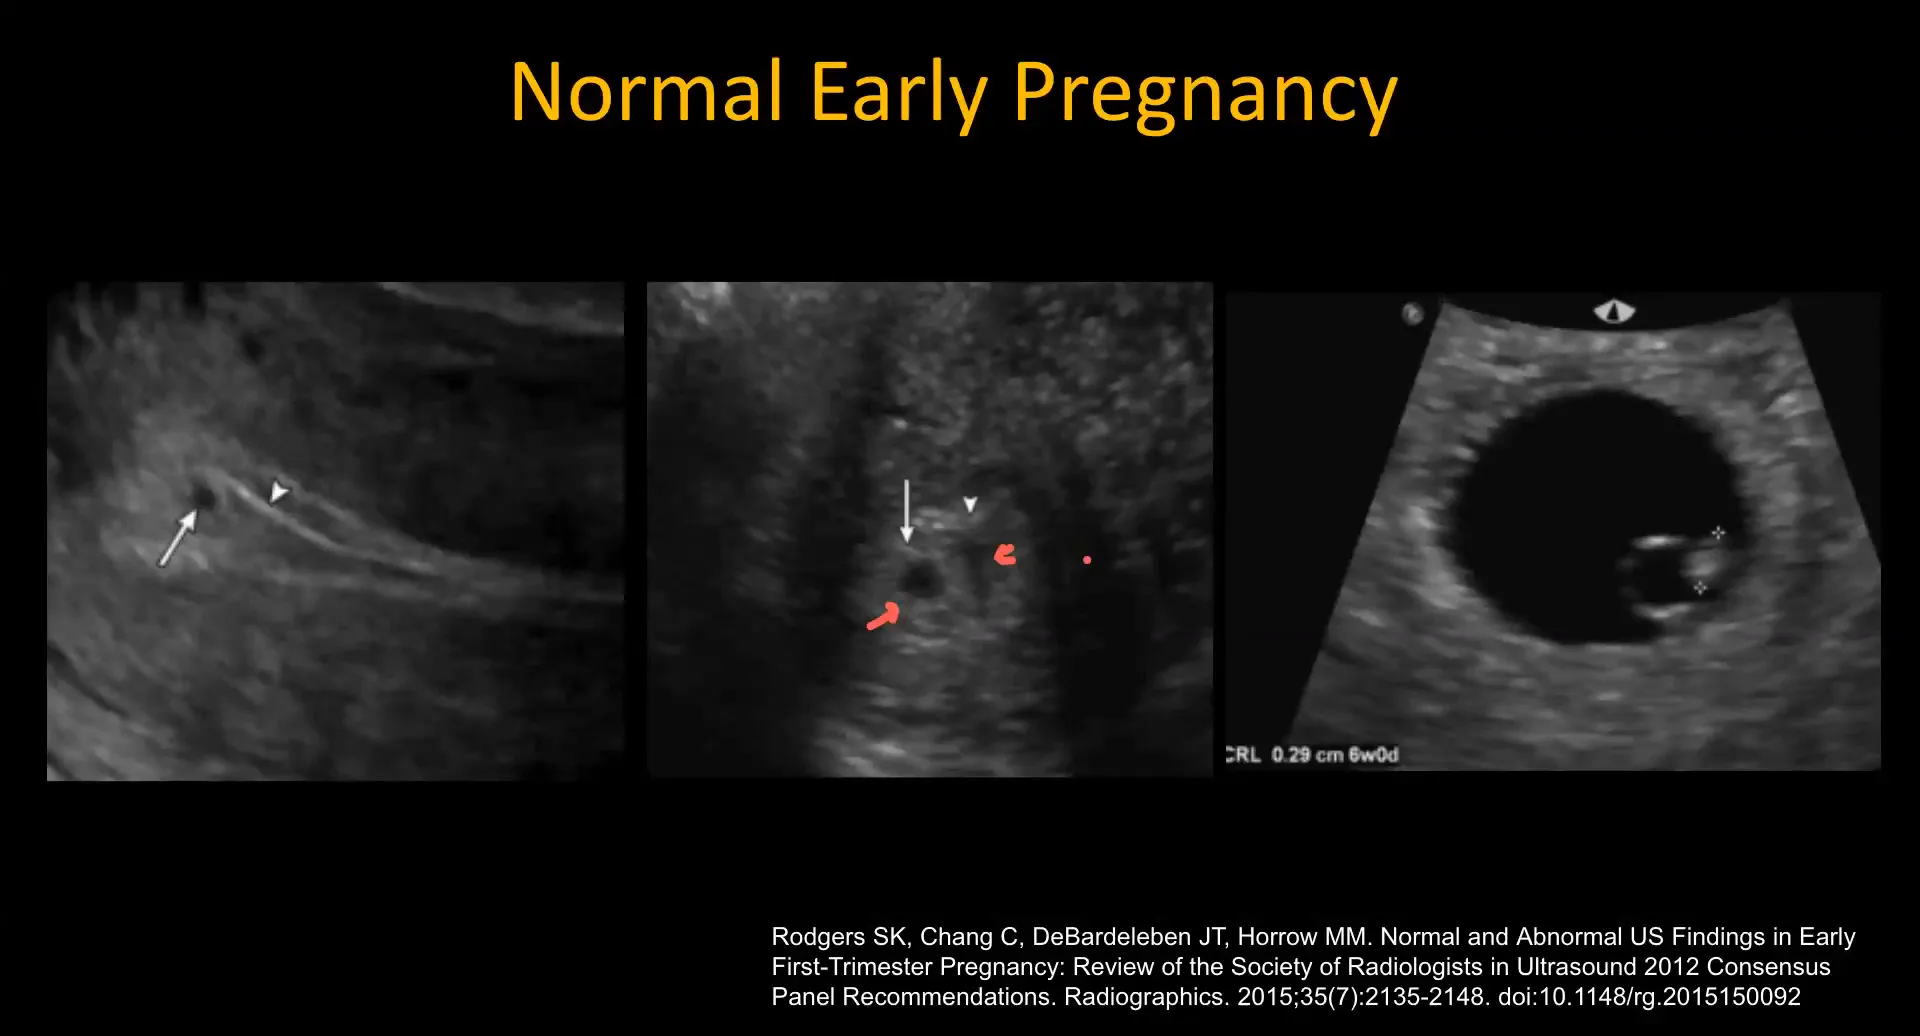

Signs of Normal Early Pregnancy

In a normal early pregnancy, several key signs can be identified on ultrasound. The intradecidual sign indicates an eccentrically located gestational sac within the echogenic decidua. Additionally, the double sac sign features two concentric echogenic rims surrounding a small fluid collection, representing the decidual reaction.

The most common normal findings include:

- Small fetal pole

- Yolk sac

- Normal-sized gestational sac